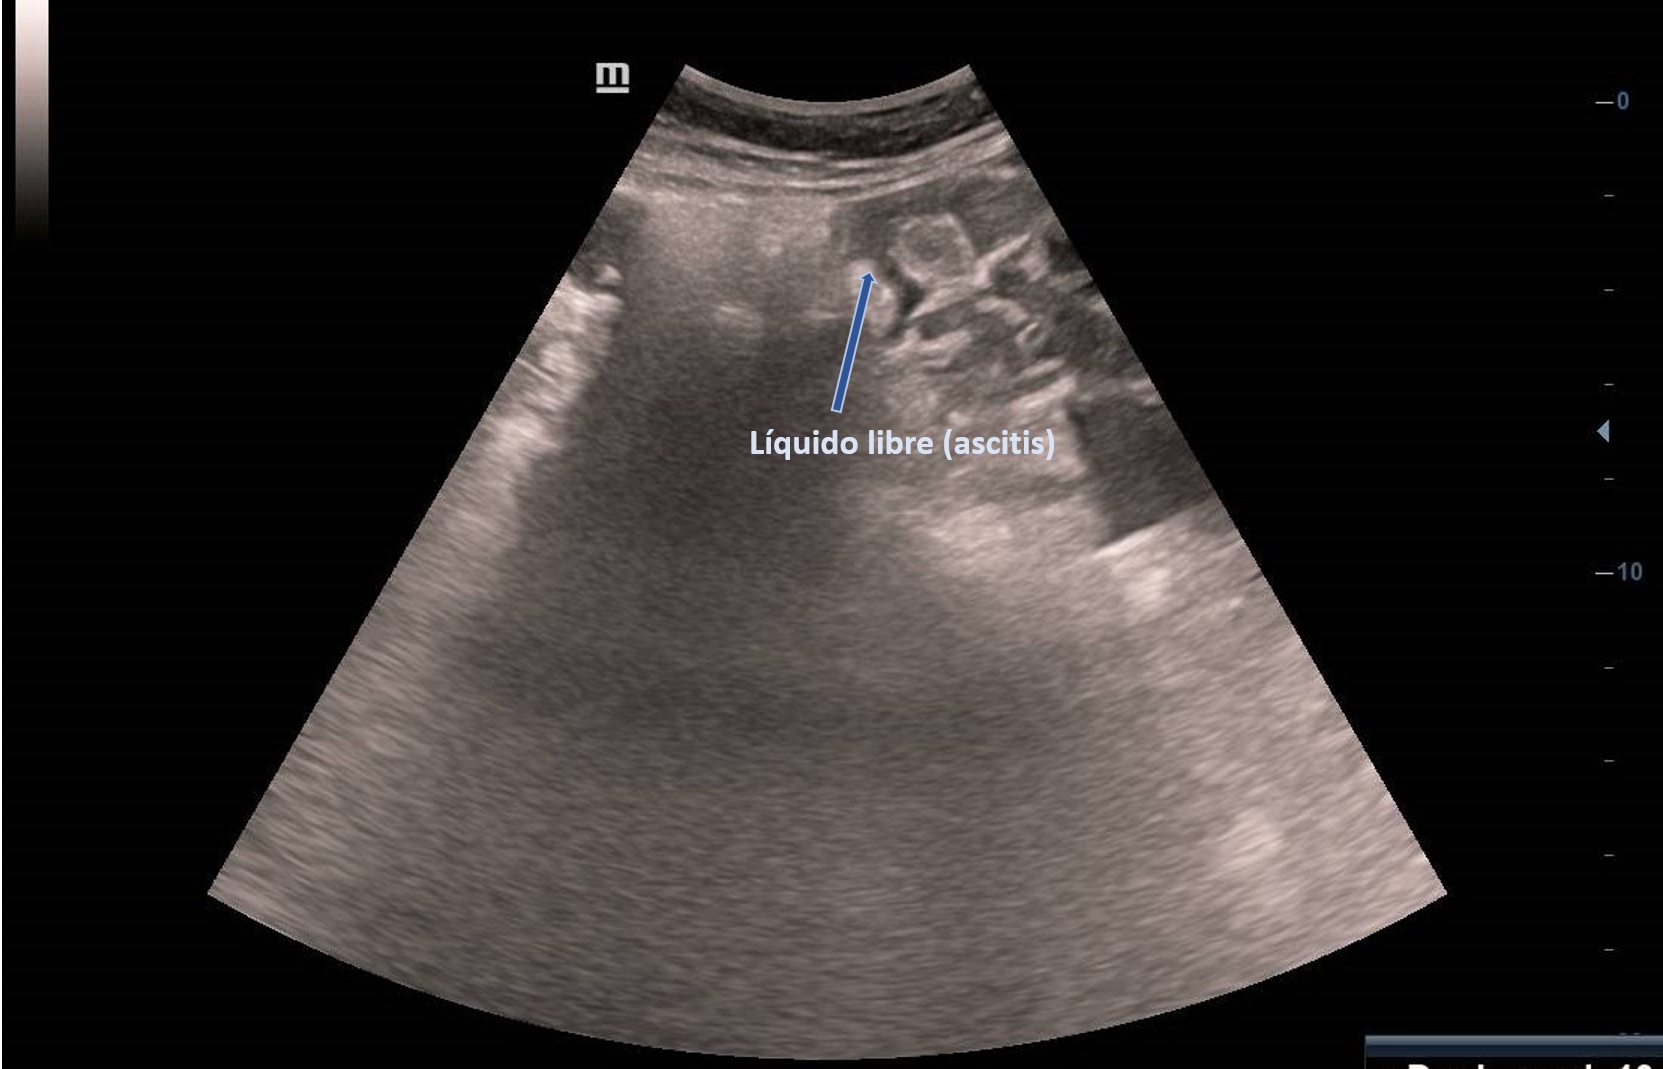

Ecografía abdominal en Atención Primaria: masa derecha adyacente a vejiga, vascularizada, de ecogenicidad heterogénea de unos 6 cm sin quedar clara dependencia del ovario derecho con imagen hipoecogénica en pelvis sugerente de ascitis. Se deriva paciente a ginecología preferente donde se realiza ecografía transvaginal: Tumoración anexial derecha, contorno irregular sugerente de neoplasia.

El EO se puede clasificar como benigno o maligno dependiendo de las características histológicas. En la ecografía aparece como una masa sólida heterogénea. No existen características ecográficas distintivas exclusivas. Ocasionalmente hay ascitis.